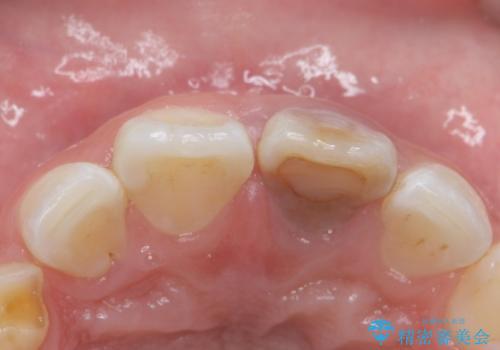

変色した前歯 ジルコニアクラウンでの修復

- 前歯の変色を主訴に来院された患者様です。

根管治療からのやり直しをした後、ジルコニアクラウンで色調の改善をしていきます。

歯の黒ずみを完全に見えなくすることができ、大変喜んでいただけました。

被せ物を装着する際は、歯の中(根管)から綺麗にすることも重要となります。